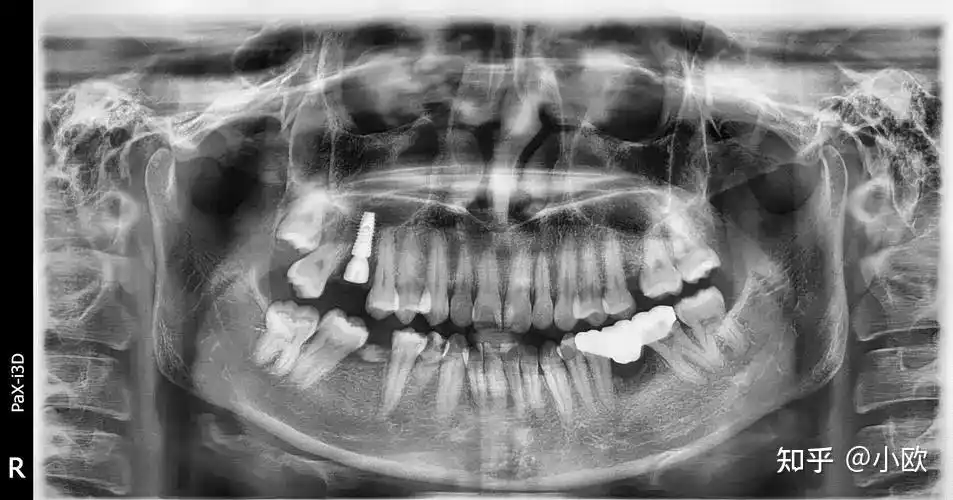

牙科常用的 x 光片主要有三种:小牙片,全景片和口腔cbct .

拍牙片前你需要知道的二三事

科普拍牙片到底会不会受到辐射